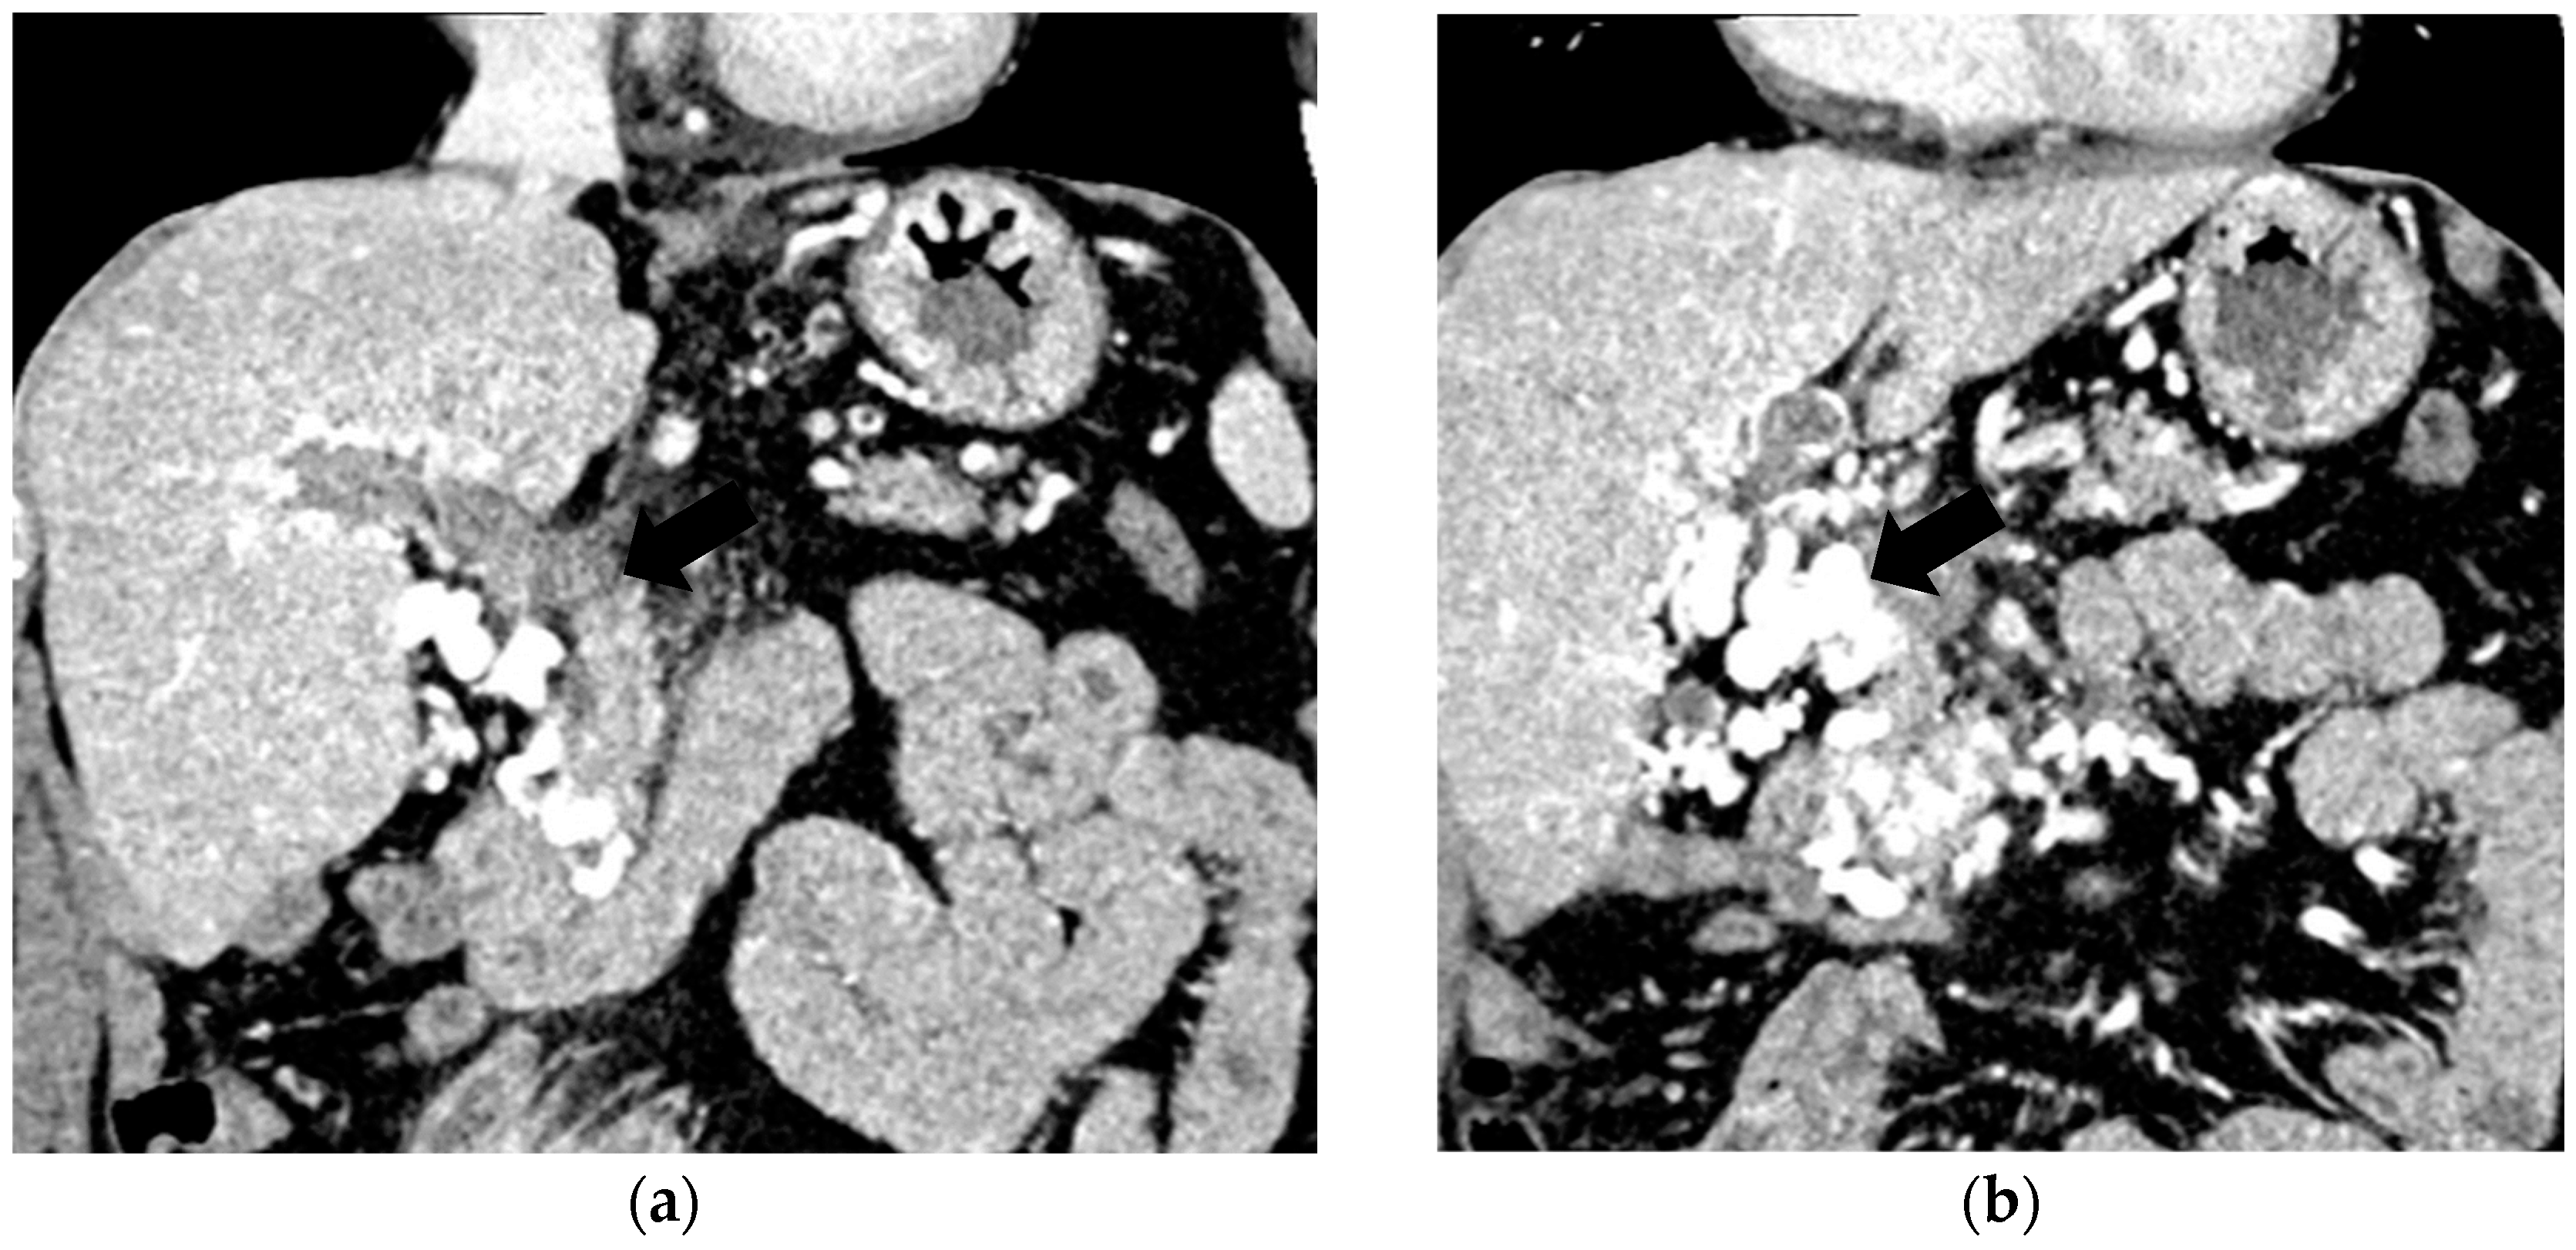

The diagnosis of PVT and PC is made by imaging procedures (transabdominal ultrasound with a Doppler or contrast-enhancing computed tomography scan, magnetic resonance imaging, or angiography in the case of therapeutic intended procedures) [1,3,12,13,14,21,29]. Transabdominal ultrasound is a reliable procedure in 60–100% of cases, with an anechoic aspect in recent cases (requiring Doppler examination or CEUS) and a hypoechoic or hyperechoic aspect in chronic cases [22,29]. Doppler examination may show an anechoic or hypoechoic thrombus and a slower (<15 cm/sec) or absent portal blood flow, and is considered the gold standard (color Doppler) for the diagnosis of PC [1], with a sensitivity and specificity of 95% (Figure 1 and Figure 2) [22]. CEUS can help the diagnosis of benign or malignant PVT, can characterize associated focal liver lesions [30], allows a better characterization of PVT [31], and also permits better detection of PC—Figure 3 and Figure 4 [32]. CT scan and MRI (Figure 5 and Figure 6) are more accurate for the evaluation of liver causes (HCC, abscesses, and other tumors) or other local causes (pancreatitis, diverticulitis, and appendicitis), and for complications (bowel infarction or perforation), and may show permeability of the portal venous system and the flow direction [1,22]. Malignant PVT has intra-thrombus arterial signals on CT, MRI, and/or CEUS, with portal vein diameter frequently 23 mm or above, and with the presence of the tumor at imaging examination (Figure 4 and Figure 6) [21].

Figure 3.

CT scan in a patient with recent surgery for transverse colon adenocarcinoma. (a) The enlarged portal vein, with intraluminal thrombus and peri-gastric collateral circulation, indicated by black arrow. (b) A 59/34 mm portal cavernoma, indicated by black arrow.

Figure 4.

MRI scan in a patient with pancreatic carcinoma. (a) Enlarged portal vein, with intraluminal thrombus. (b) A hilar 5.1/3.3 cm portal cavernoma.

Transabdominal ultrasound with Doppler protocol (Figure 1a,b and Figure 2a,b), CT scan (Figure 3a,b), and MRI (Figure 4a,b) were used for the diagnosis in 88.9, 75.1, and 15% of cases, respectively. CEUS was used for the diagnosis in 49 cases (25.9%) but in only 29 cases was it used for the evaluation of the thrombus, and in two cases for cavernoma diagnosis (Figure 5a,b and Figure 6a,b).